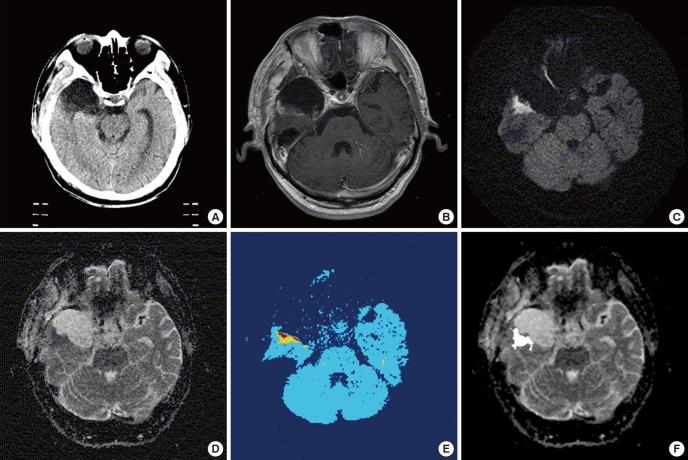

Based on the assumption that apparent diffusion coefficients (ADCs) define high-risk clinical target volume (aCTVHR) in high-grade glioma in a cellularity-dependent manner, the dosimetric effects of aCTVHR-targeted dose optimization were evaluated in two intensity-modulated radiation therapy (IMRT) plans. Diffusion-weighted magnetic resonance (MR) images and ADC maps were analyzed qualitatively and quantitatively to determine aCTVHR in a high-grade glioma with high cellularity. After confirming tumor malignancy using the average and minimum ADCs and ADC ratios, the aCTVHR with double- or triple-restricted water diffusion was defined on computed tomography images through image registration. Doses to the aCTVHR and CTV defined on T1-weighted MR images were optimized using a simultaneous integrated boost technique. The dosimetric benefits for CTVs and organs at risk (OARs) were compared using dose volume histograms and various biophysical indices in an ADC map-based IMRT (IMRTADC) plan and a conventional IMRT (IMRTconv) plan. The IMRTADC plan improved dose conformity up to 15 times, compared to the IMRTconv plan. It reduced the equivalent uniform doses in the visual system and brain stem by more than 10% and 16%, respectively. The ADC-based target differentiation and dose optimization may facilitate conformal dose distribution to the aCTVHR and OAR sparing in an IMRT plan.

基于表观扩散系数(ADC)以细胞密度依赖方式定义高级别胶质瘤的高风险临床靶区(aCTVHR)这一假设,在两个调强放射治疗(IMRT)计划中评估了以aCTVHR为靶区的剂量优化的剂量学效果。对扩散加权磁共振(MR)图像和ADC图进行定性和定量分析,以确定细胞密度高的高级别胶质瘤中的aCTVHR。在使用平均和最小ADC以及ADC比值确认肿瘤恶性程度后,通过图像配准在计算机断层扫描图像上定义具有双重或三重受限水扩散的aCTVHR。使用同步整合加量技术优化在T1加权MR图像上定义的aCTVHR和临床靶区(CTV)的剂量。在基于ADC图的IMRT(IMRTADC)计划和传统IMRT(IMRTconv)计划中,使用剂量体积直方图和各种生物物理指标比较CTV和危及器官(OAR)的剂量学益处。与IMRTconv计划相比,IMRTADC计划将剂量适形性提高了15倍。它分别将视觉系统和脑干中的等效均匀剂量降低了10%以上和16%以上。基于ADC的靶区分化和剂量优化可能有助于在IMRT计划中实现向aCTVHR的适形剂量分布和OAR保护。